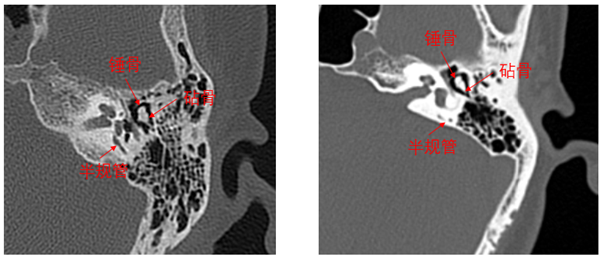

Precision 32精密斷層能譜 CT完全由開普影像自主研發(fā),擁有多項(xiàng)自主知識(shí)產(chǎn)權(quán)和多項(xiàng)專利。作為開普影像第一款CT旗艦產(chǎn)品,Precision 32CT擁有精密斷層掃描專利技術(shù)PAxial——采用創(chuàng)新的掃描方式增加患者縱向采樣,結(jié)合精密的重建算法,從數(shù)據(jù)采樣和圖像重建兩個(gè)領(lǐng)域共同實(shí)現(xiàn)縱向超高分辨率圖像重建,顯著提高細(xì)微病變的檢出率。全球發(fā)明專利精密斷層掃描技術(shù)PAxial使Precision 32CT能得到僅0.275mm的業(yè)內(nèi)超精細(xì)圖像,在內(nèi)耳成像和肺小結(jié)節(jié)探查等應(yīng)用中有明顯優(yōu)勢(shì),全面助力精準(zhǔn)診斷。比如,內(nèi)耳成像領(lǐng)域除了能看清聽小骨及耳蝸等內(nèi)耳結(jié)構(gòu)外,甚至連內(nèi)耳各結(jié)構(gòu)之間的關(guān)系都清晰可見。

Precision 32CT0.275mm精密內(nèi)耳圖像?普通CT0.5mm薄層內(nèi)耳圖像